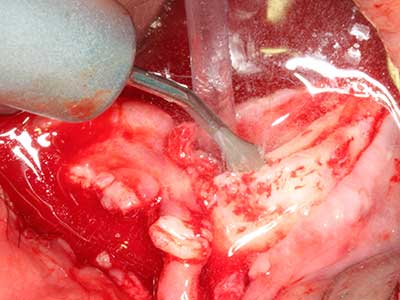

Piezosurgery has additional advantages when harvesting bone blocks. In addition to the high precision with osteotomy described above, the use of the thin saw tips specifically minimizes loss of material. Greater loss of material during harvesting can be expected with the thicker instrument tips, particularly when using Lindemann drills (Lakshmiganthan, Gokulanathan et al. 2012). The basal separation, which is necessary particularly for retromolar block transplants, is simplified by specially designed rectangular saws, with the result that piezosurgery is viewed as a precise, simple and safe procedure for harvesting retromolar bone blocks (Happe 2007) (Fig. 1-12).